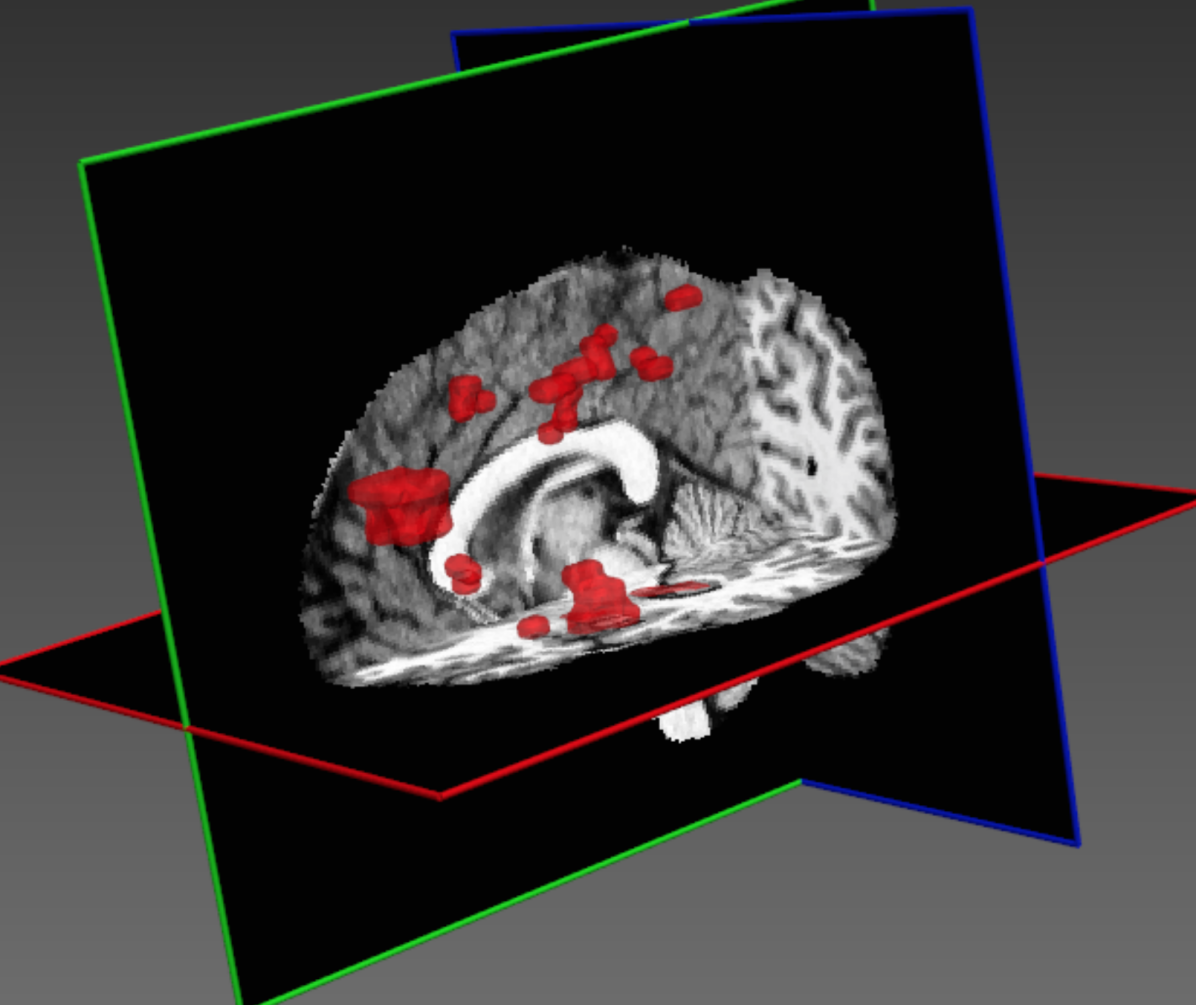

The performance of our system on the training data is shown in Table 4. Significant improvement is achieved by the structural regularisation offered by the CRF, although it could be partially accounted for by overfitting the training data during the CRF’s configuration. Examples for visual inspection are shown in Fig. 13.

Refer to caption

Figure 13: Examples of segmentations performed by our system on the training datasets of (SISS) ISLES 2015. (top and middle) The system is capable of satisfying segmentation of both large and smaller lesions. (bottom) Common mistakes are performed due to the challenge of differentiating stroke lesions from White Matter lesions.